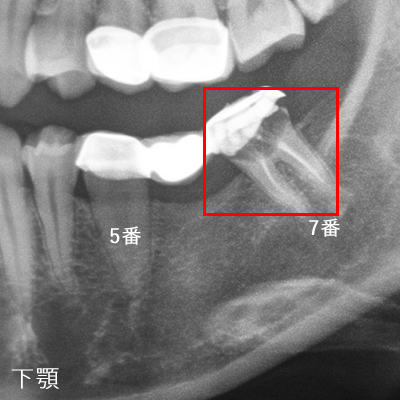

インプラントでもっとも危険なトラブルは血管や神経の損傷です。

インプラントを埋入する骨の中やその周囲には神経や大きな血管が走行しており、手術中にそれらを損傷すると大出血や知覚麻痺を起こす可能性があります。

これらを回避するにはCT等を使った診査診断や解剖学的形態の把握が重要になります。

当院ではインプラント治療を行う前には必ずCT撮影、模型診断を行い、安全にインプラント治療が行える状態かを診断してから手術を行います。